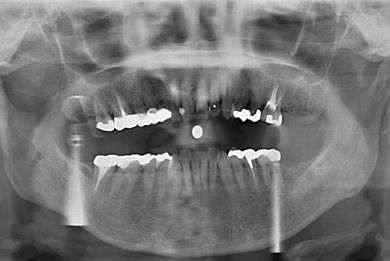

性別/年齢 女性 / 53歳

主訴 噛むと痛い。(咬合痛がある)

治療内容 ハイブリッドセラミック1本

治療部位

4

総治療費 75,705円

治療期間 1ヶ月